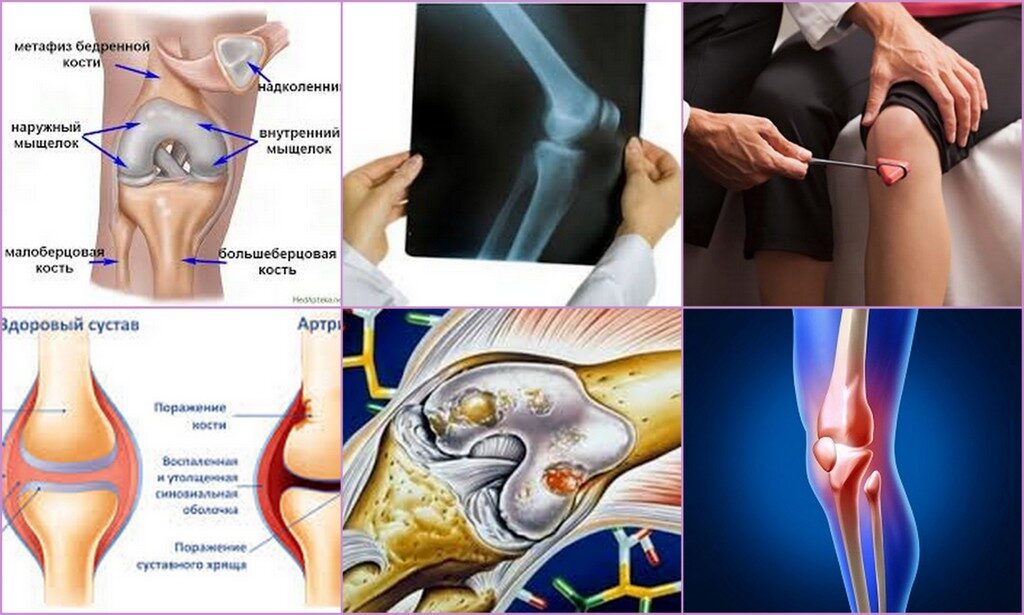

Медицинские состояния: Септический артрит коленного сустава

Раздел: Мир в картинках